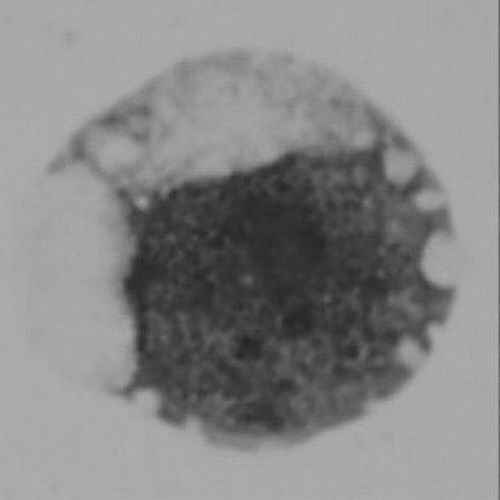

②光鏡下觀察到的人類(lèi)紅細(xì)胞終末發(fā)育的前期。

紅細(xì)胞發(fā)育過(guò)程可以分為多個(gè)階段。成熟的紅細(xì)胞通常是雙凹圓盤(pán)形且沒(méi)有細(xì)胞核,因此,在其發(fā)育過(guò)程中,前體細(xì)胞需要經(jīng)歷染色質(zhì)壓縮、細(xì)胞核極化等過(guò)程,哺乳動(dòng)物的紅細(xì)胞最終還要經(jīng)歷“脫去細(xì)胞核”的關(guān)鍵步驟,以產(chǎn)生沒(méi)有細(xì)胞核的紅細(xì)胞。

李湘盈介紹,科學(xué)家早就觀察到紅細(xì)胞在成熟過(guò)程中體積變小,伴隨其染色質(zhì)逐漸壓縮,核容量最終減少到原來(lái)的1/3。而整個(gè)過(guò)程中仍然需要保持血紅蛋白基因等紅細(xì)胞功能相關(guān)基因的表達(dá)。“紅細(xì)胞發(fā)育中的染色質(zhì)壓縮過(guò)程是否有一定的程序性規(guī)律與機(jī)制,以及染色質(zhì)高度壓縮狀態(tài)下如何維持基因表達(dá),一直是懸而未決的問(wèn)題?!崩钕嬗f(shuō)。